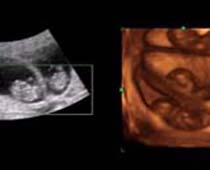

Clips vidéo 4D scan ultrason fœtal | Dr N Layyous

Clips vidéo 4D scan ultrason fœtal